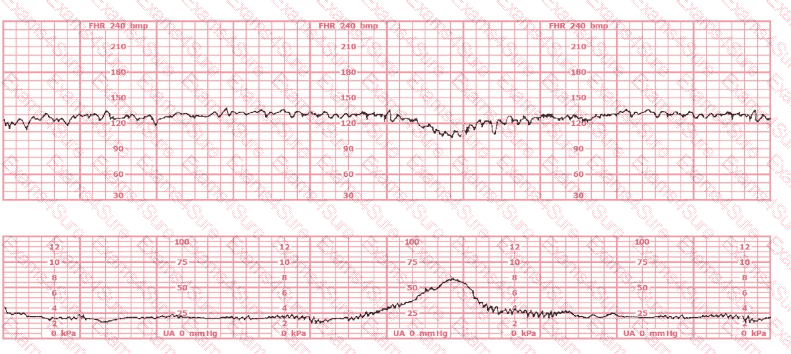

A woman (G1, P0) at 41-weeks gestation presents to OB triage to rule out labor. Her cervical exam is 1 cm/50%/-2. Membranes are intact. She would like to go home if not in labor. Based on this tracing, which represents the last two hours, the best approach is: